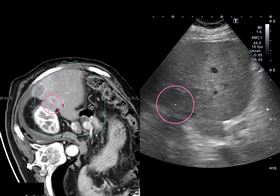

因禍得福!她車禍意外揪直腸藏10CM腫瘤

台中一名44歲張姓女子,因發生車禍送醫,安排腹部電腦...

2026/03/04 14:09

婦出車禍反保命 意外揪出直腸長腫瘤

44歲張婦因車禍送醫安排腹部電腦斷層檢查,結果意外發...

2026/03/04 12:58